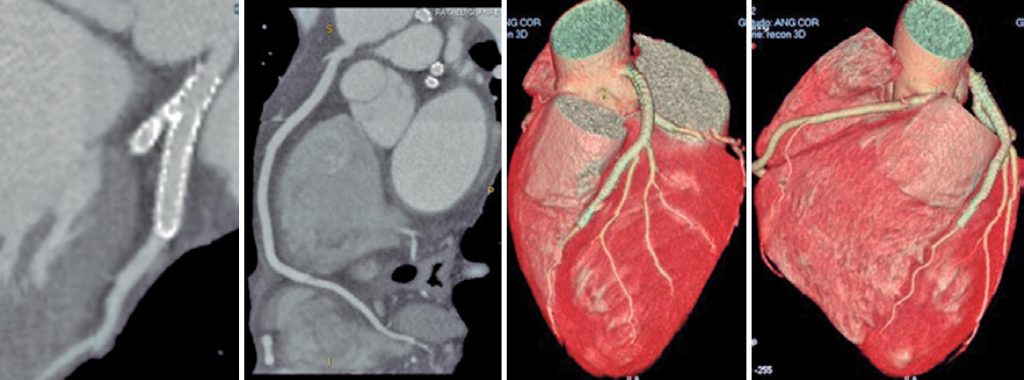

Figure 6

Control coronary computed tomography angiography 15 months after the procedure without signs of in-stent restenosis.